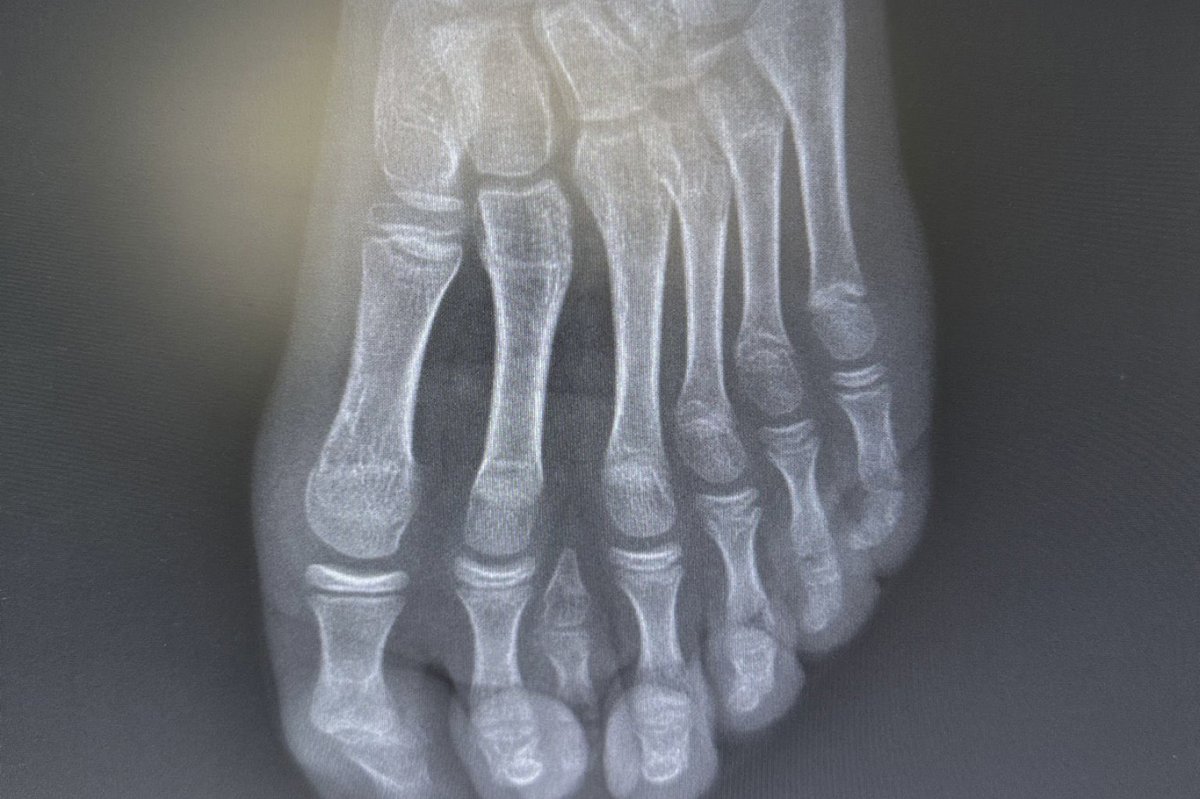

Genel yaklaşımda bu tür vakalarda cerrahi planlamanın ayağın beş parmaklı anatomik yapısına uygun şekilde yapıldığı ifade edildi. Ancak hastanın yapılan detaylı klinik ve radyolojik değerlendirmelerinde altı parmağın; falanks (parmak kemikleri), metatars (tarak kemikleri) ve diğer ayak kemikleri ile uyumlu ve düzgün şekilde geliştiği tespit edildi.

Uzmanlar, mevcut altı parmağa müdahale edilmesinin ayak biyomekaniğini ve dengesini olumsuz etkileyebileceğini değerlendirdi.

Bu doğrultuda cerrahi planlama yeniden yapılarak, fonksiyonel açıdan yetersiz ve estetik olarak problem oluşturan tek parmağın çıkarılmasına karar verildi. Operasyon sırasında diğer parmaklara ait damar ve sinir yapıları titizlikle korunurken, mikrocerrahi teknikler kullanılarak işlem sorunsuz şekilde tamamlandı.